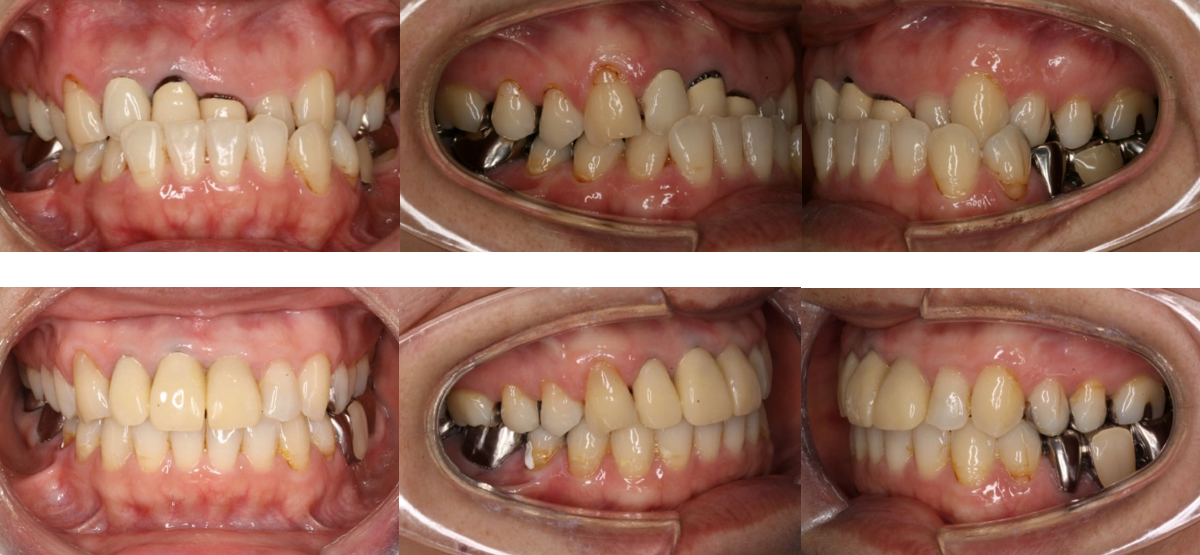

受け口の治療前

受け口の治療後

上の写真のように、以前であれば外科矯正を行ったようなケースでも、今はインプラント矯正によって、受け口(下顎前突)や、オトガイ部の突出感も改善できることがあります。

①受け口(下顎前突)の矯正治療例(50代女性・治療期間2年2か月)

| 年齢・性別 | 50代女性 |

| 治療期間 | 2年2か月 |

| 抜歯 | なし |

| 治療費 | 100万円(調整費、保定費まで含む総額制) |

| 備考 | 裏側矯正、QH拡大、歯冠長延長術、補綴物再作製 |

| リスク・副作用 | 痛み・治療後の後戻り・歯根吸収・歯髄壊死・歯肉退縮 |